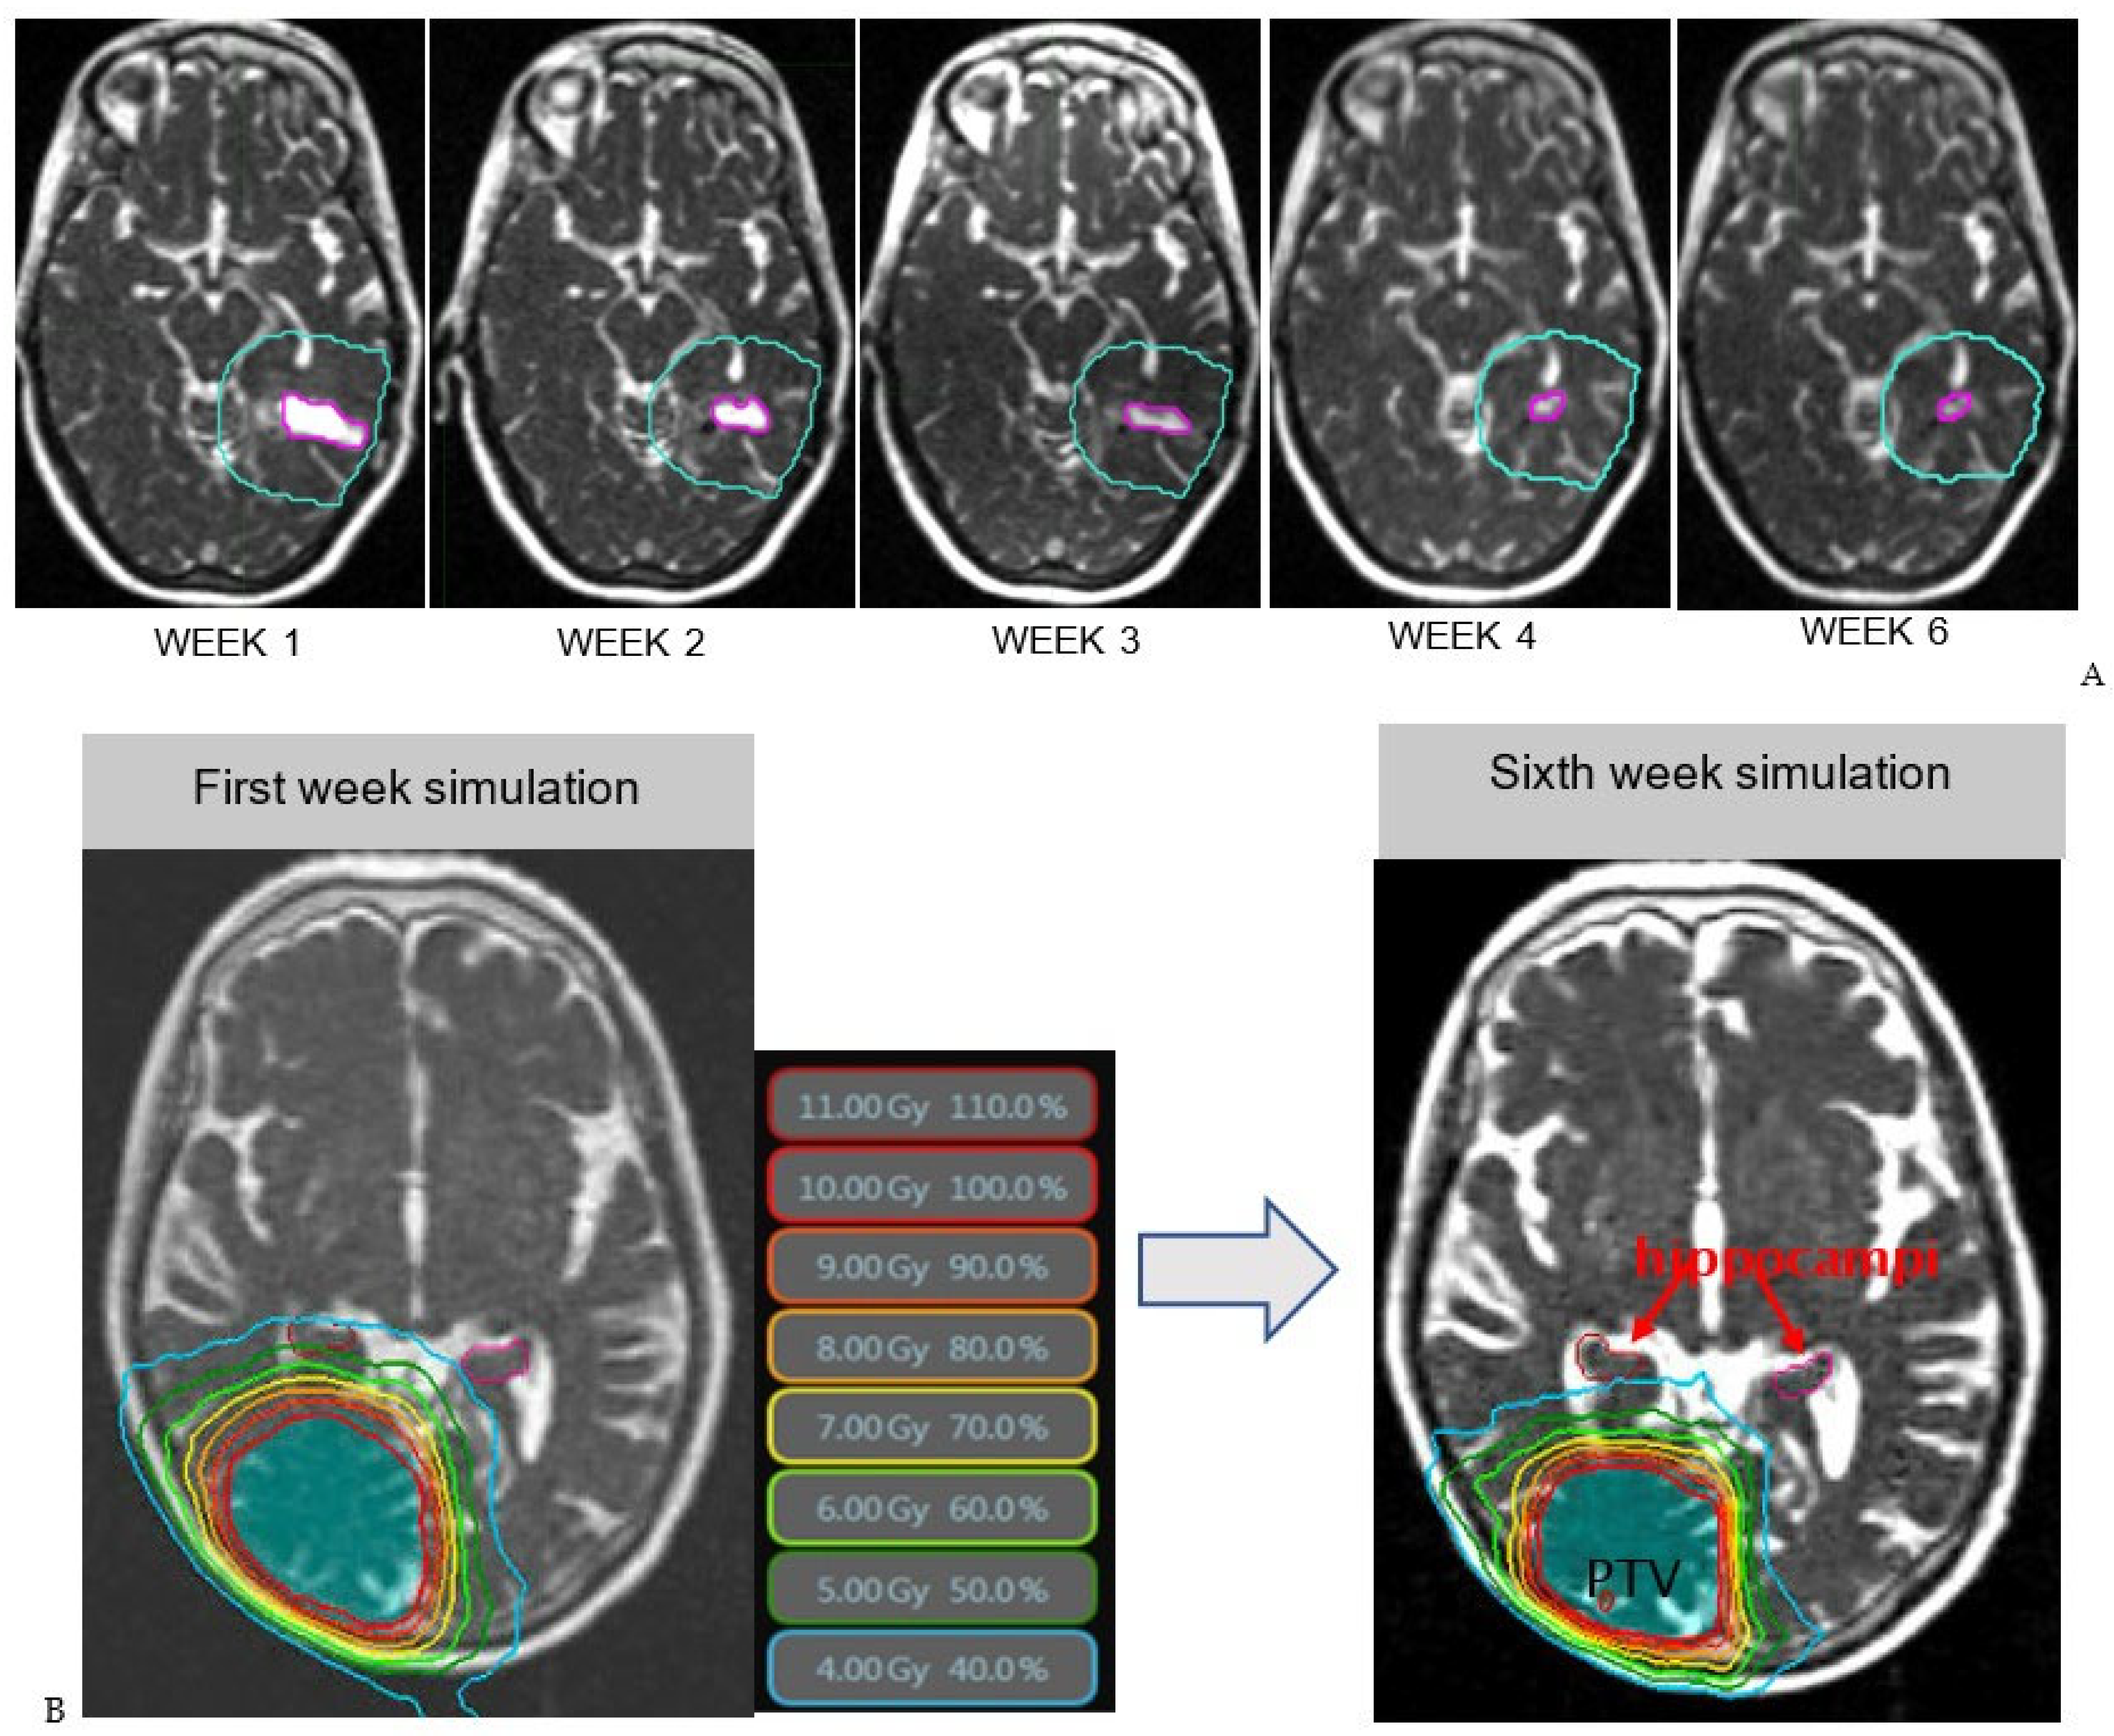

2. Materials and Methods

2.1. Daily Set up Images

2.2. Patient Data Base and Analysis

3. Results